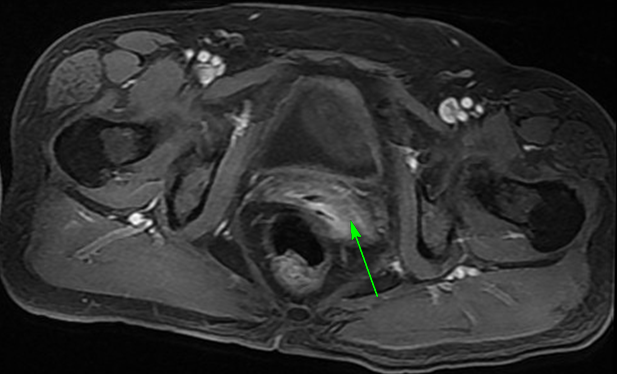

1、B超:内膜厚0.5cm,子宫多发肌瘤,较大者1.5*1.4cm,宫腔下段至宫颈管内见低回声,约1.9*1.9*2.8cm,请结合临床除外占位病变; 2、诊刮术,病理回报:低分化癌,符合透明细胞癌; 3、盆腔MRI:子宫内膜不规则增厚,结合带显示欠清,宫底部短T2结节影,肌瘤可能,宫颈饱满,后壁片状长T2信号。